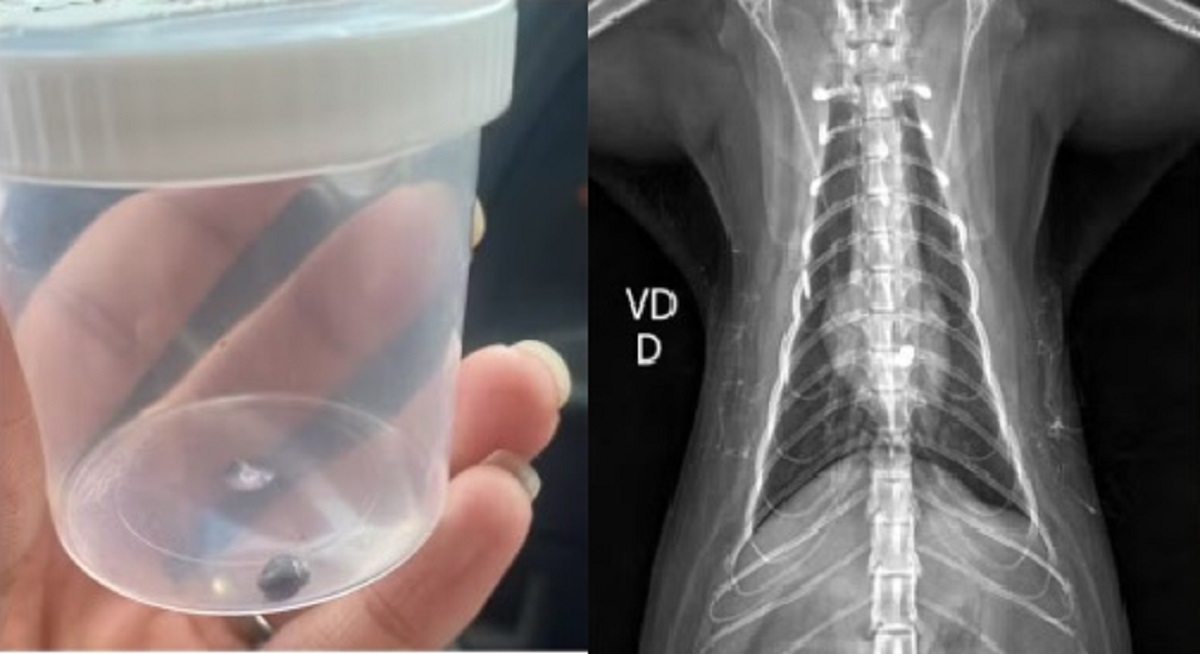

Depois de fazer o raio x, no dia seguinte, se apontou um projétil de chumbinho na medula espinhal da gata. E a veterinária falou do risco de se perder o movimento das patas traseiras por conta do tiro.

Já neste último sábado (31), Lua teve que passar por uma cirurgia, onde se retirou o projétil. E, depois disso, ficou consumado que a gatinha não poderá mais andar e ainda terá que fazer fisioterapia.